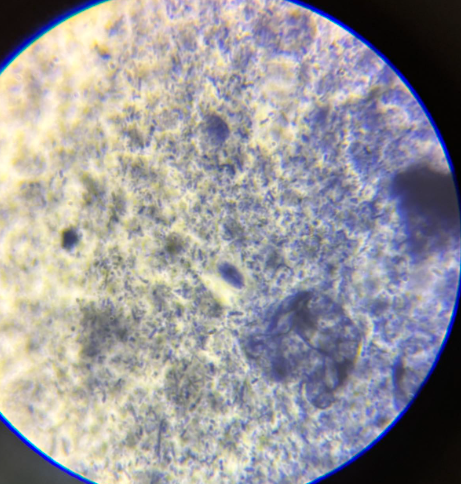

acanthamoeba sp trofozoity